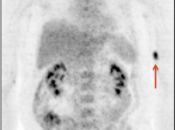

Extravasation of Injected FDG

FDG is injected intravenously. As many cancer patients have challenging venous access issues, partial extravasation of FDG during injection is not uncommon (an estimated 10% of patients have evidence of extravasation on their PET images).

Extravasation of FDG at the time of the intravenous injection can result in false positive interpretations due to:

- Focal intense uptake at the injection site.

- Linear uptake along the lymphatic channels within the arm (appearing as long vessels).

- Focal uptake in small ipsilateral axillary nodes.

If these nodes are enlarged, be cautious before dismissing them as “injection-related”. We have seen more than one case of a radiologist calling axillary nodes “injection-related”, when the patient was injected in the opposite arm.

If the volume of extravasation is large enough, it can result in a significant reduction of circulating FDG available for tumoral uptake, resulting in false negative results (“Sponge Effect”, discussed here).